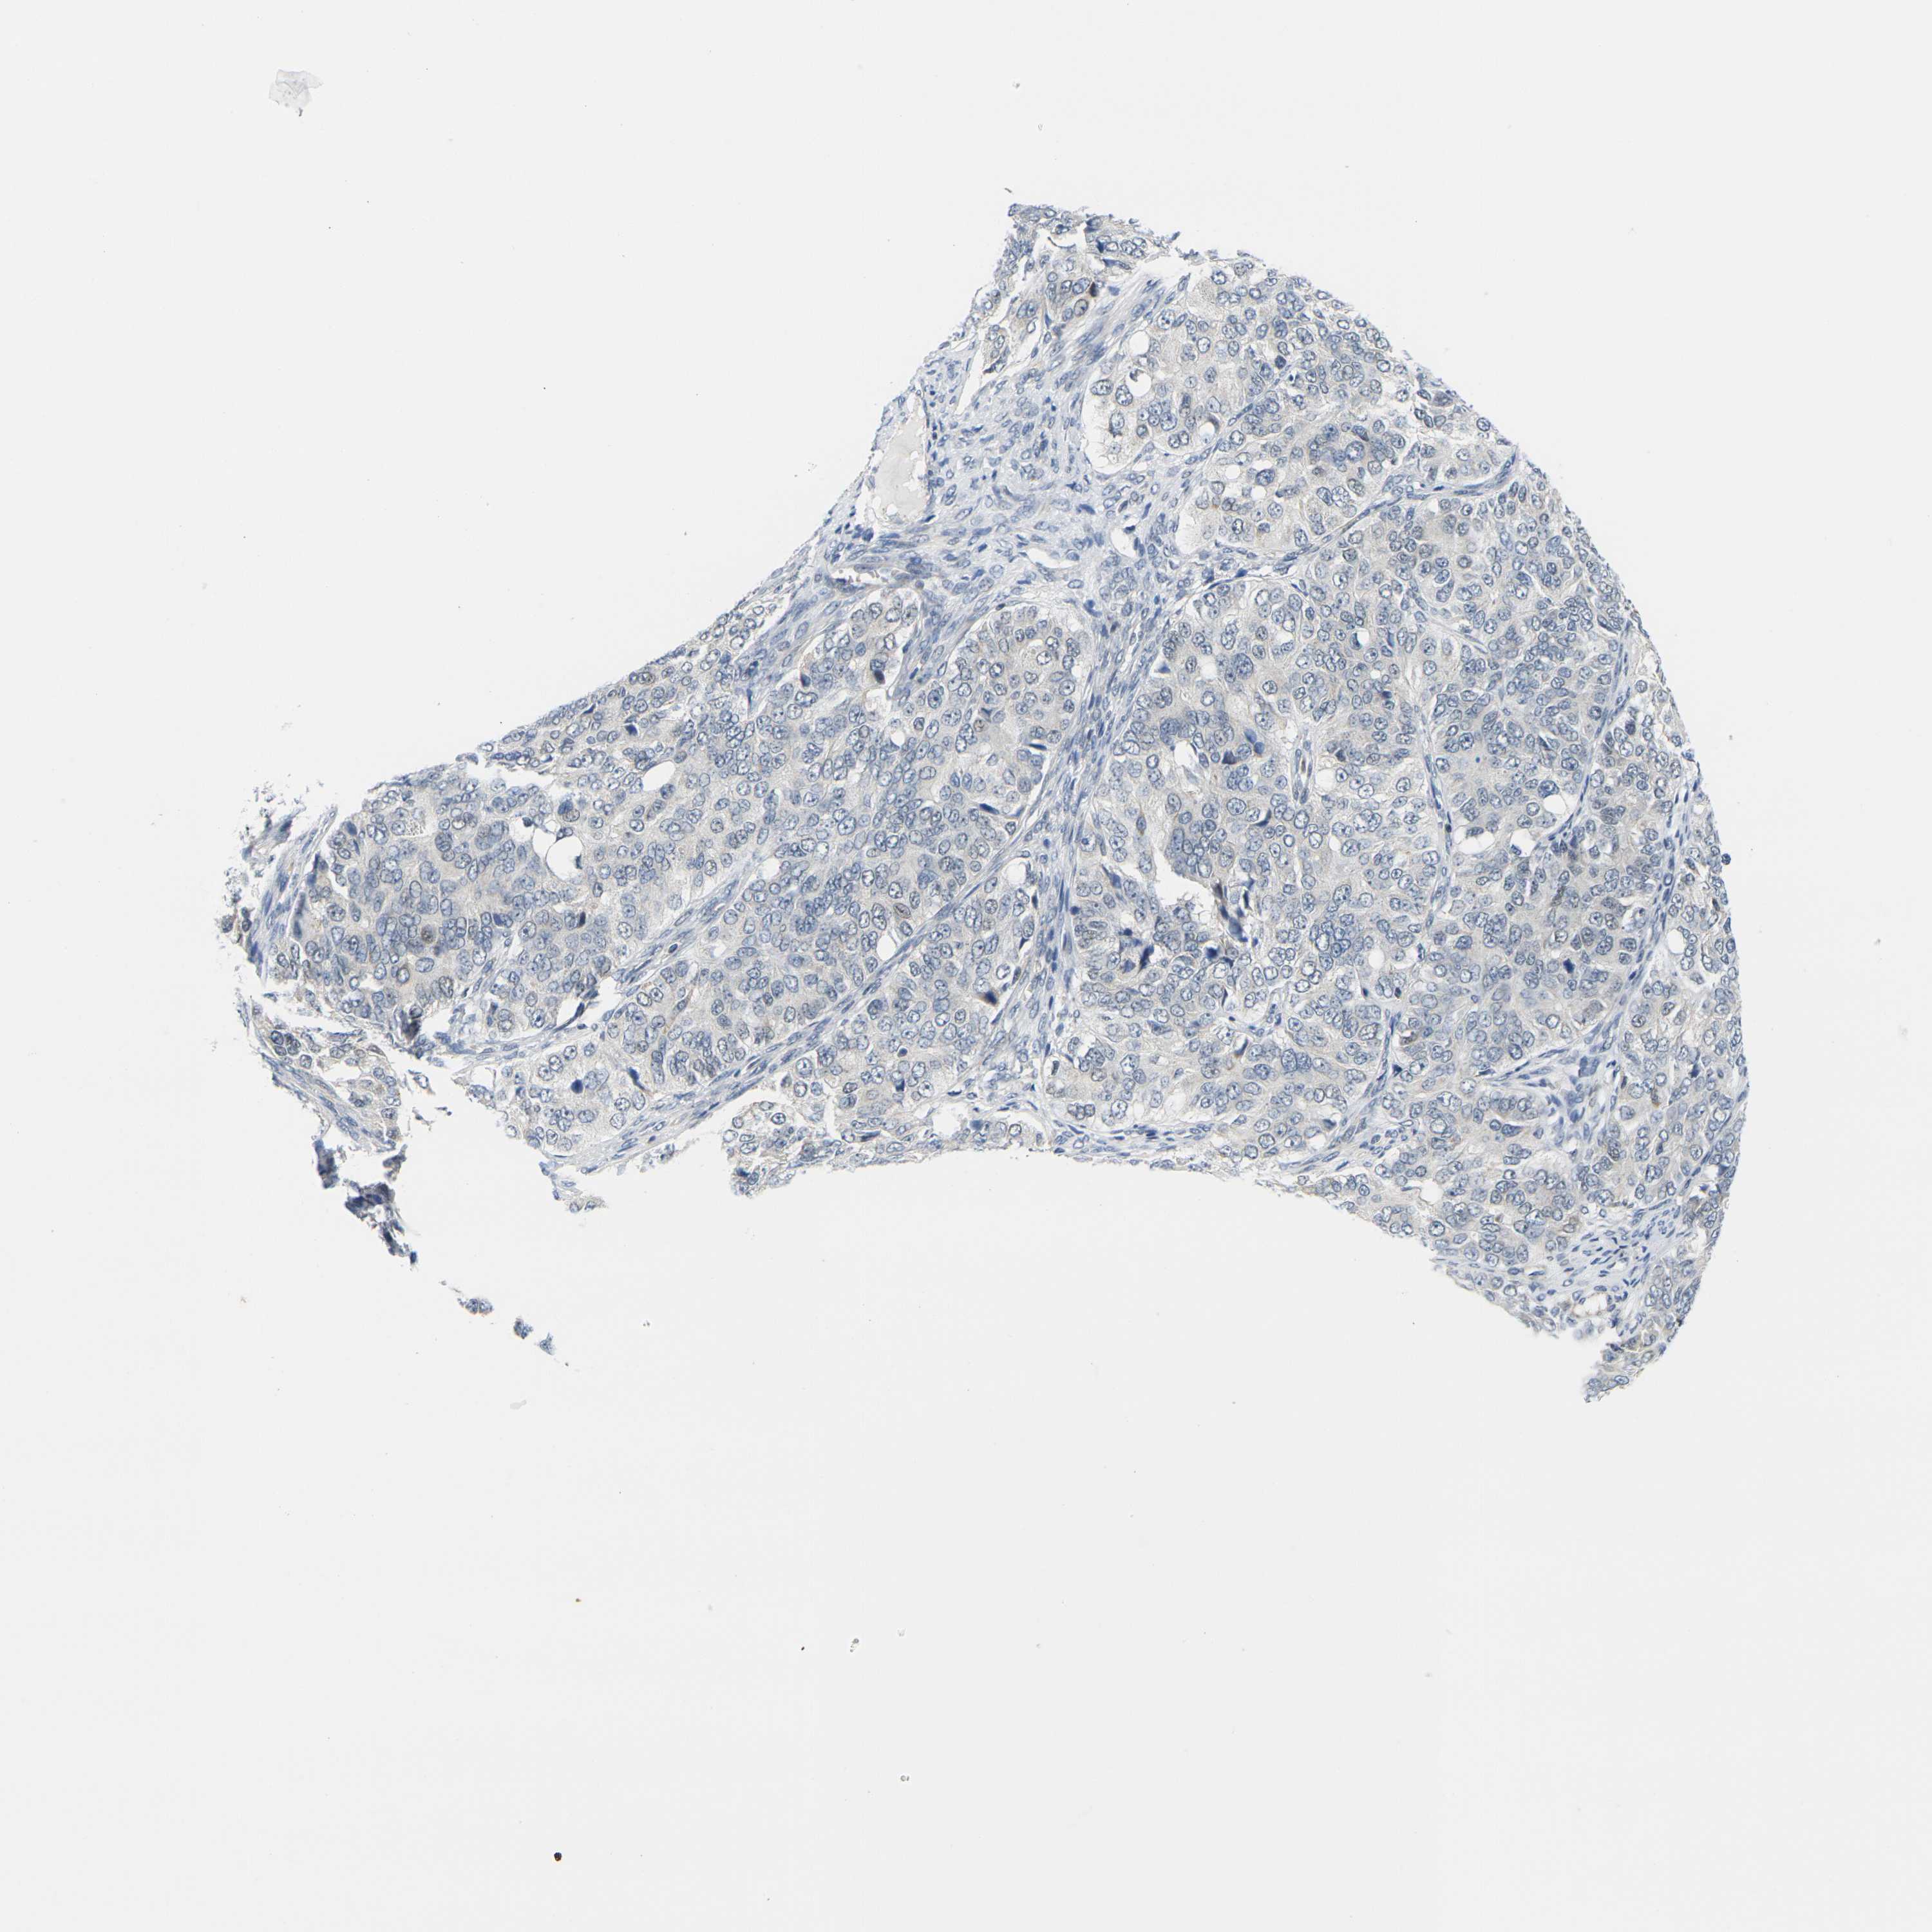

OVARIAN CANCER - Protein expressioni

A mouse-over function shows sample information and annotation data. Click on an image to view it in a full screen mode. Samples can be filtered based on level of antibody staining by selecting one or several of the following categories: high, medium, low and not detected. The assay and annotation is described here.

Note that samples used for immunohistochemistry by the Human Protein Atlas do not correspond to samples in the TCGA dataset.

Antibody stainingi

Antibody staining in the annotated cell types in the current human tissue is reported as not detected, low, medium, or high, based on conventional immunohistochemistry profiling in selected tissues. This score is based on the combination of the staining intensity and fraction of stained cells.

Each image is clickable and will lead to virtual microscopy that enables deeper exploration of all samples and also displays staining intensity scores, fraction scores and subcellular localization as well as patient and tissue information for each sample.

Antibody HPA012410

Staining

High

Medium

Low

Not detected

Intensity

Strong

Moderate

Weak

Negative

Quantity

>75%

75%-25%

<25%

None

Location

Nuclear

Cytoplasmic/membranous

Cytoplasmic/membranous,nuclear

Cystadenocarcinoma, serous, NOS

Carcinoma, endometroid

Cystadenocarcinoma, mucinous, NOS

Carcinoma, NOS